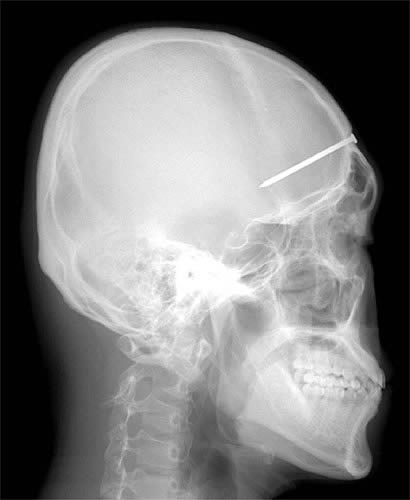

メタリカのスタンド攻撃うけてるやん

脳にダメージなければ意外と無事なのね

メタリカもそうだが、何らかのスタンド攻撃を疑うのも解らんでもないww

目に鍵はSAWみたい

21はその後矢を引き抜いて飛び出た目玉を食べそう。

以前なんかで聞いた話だけど、米国で頭を鉄棒が貫通して

穴が開いた状態で運び込まれた人が居たそうだ。

その人はその後も生きてたそうだけど、人格が変わってしまったとか。